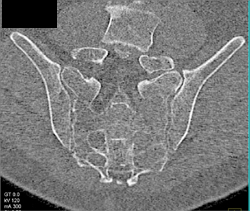

Myeloma